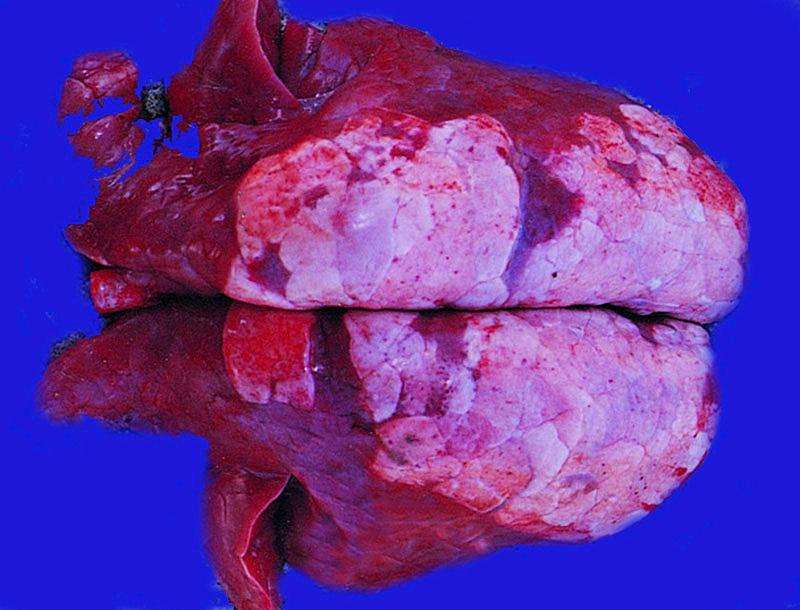

豬支原體肺炎(MPS),也稱豬地方流行性肺炎,俗稱“豬氣踹病”,是由豬肺炎支原體引起的一種接觸性慢性呼吸道傳染病。臨床特征為咳嗽和氣喘,病變特征是兩肺的尖葉、心葉、中間葉和隔葉呈對(duì)稱性肉樣或蝦肉樣實(shí)變。豬支原體肺炎主要臨床癥狀是豬感染后發(fā)生慢性干咳、生長(zhǎng)受阻、發(fā)育遲緩、發(fā)病率高、死亡率低以及擴(kuò)散緩慢,易反復(fù)發(fā)作。